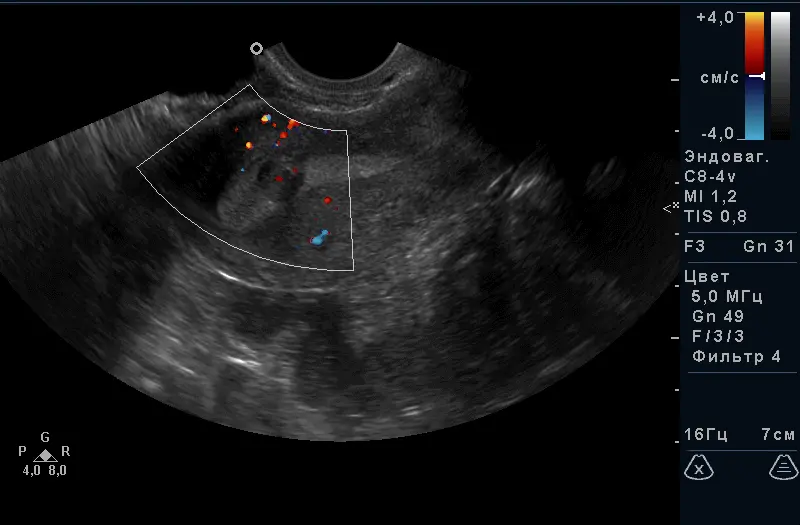

Ультразвукове дослідження органів малого таза – це найдоступніший і абсолютно безпечний метод обстеження. Унікальністю використання ультразвуку в діагностиці гінекологічних захворювань є отримання зображень з високою роздільною здатністю, що дає можливість оцінити не тільки структуру пухлиноподібних утворень, а й оцінити характеристику щільності і кровопостачання.

За допомогою УЗД можна побачити і оцінити стан тіла матки, шийки матки, яєчників, маткових труб (при їх патології) і оточуючих їх органів. Є пріоритетним методом дослідження стану судин малого таза. Під час дослідження вимірюються розміри всіх доступних для дослідження органів, оцінюється їх структура і відповідність фазі менструального циклу, оцінка кровопостачання органів і судин.